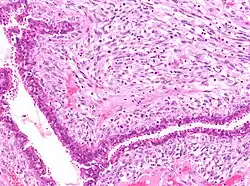

![]() | Squamous cell carcinoma of cervix | Invasive Squamous Carcinoma of the Cervix. Cold Knife Cone. | Category: Histopathology of squamous cell carcinoma of the cervix | Invasive squamous carcinoma of cervix |